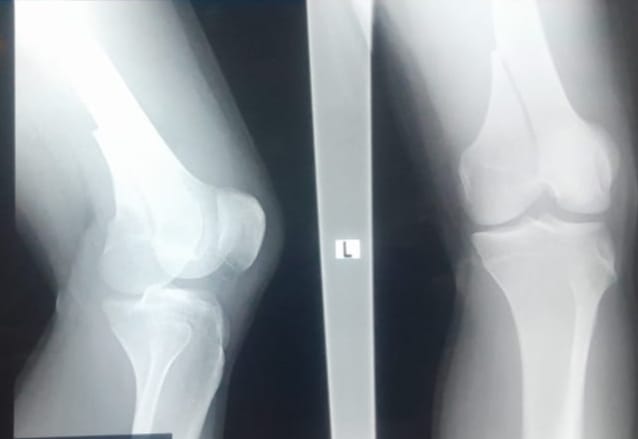

Simalungun, Radarkriminaltv.com – Kamis, (30/10/2025) akibat mencuri brondolan kelapa sawit satu goni di Kebun PTPN IV Unit Marihat, Afdeling VI Pondok Malasia, diduga pelaku telah dianiaya hingga mengalami memar dan patah kaki, pada hari Jum’at , (24/10/2025) yang lalu.

Berdasarkan penuturan korban kepada pelapor, “Bahwa korban dikeroyok dengan mata ditutup lakban dan tangan diborgol ke belakang. Dalam keadaan tersebut korban menyatakan ada yang memukul hingga korban terjatuh dan dilindas sepeda motor. Merasa tidak terima dan keberatan atas perlakuan yang dialami adik pelapor, akhirnya pelapor mengadukan kejadian tersebut ke Polres Simalungun agar kejadian tersebut diproses sesuai dengan hukum yang berlaku di NKRI.”